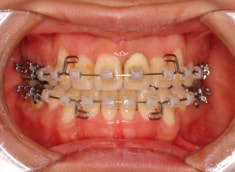

治療法:表の矯正(T21ブラケット)

治療開始時